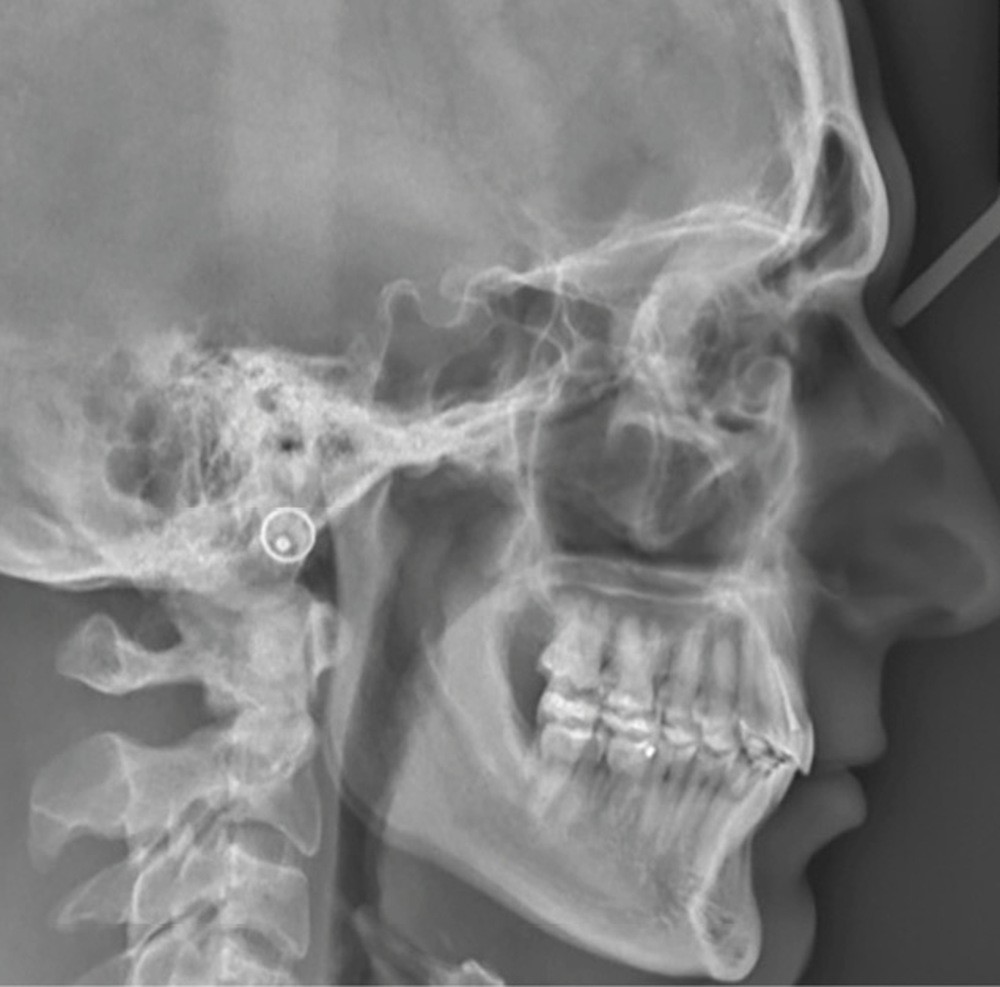

Examens complémentaires (fig. 3)

La téléradiographie de profil et l’analyse céphalométrique montrent une classe I squelettique tendance classe II dans un contexte d’hypodivergence, caractéristique des classes II division 2 [3,4]. L’axe de l’incisive mandibulaire est correct, au sein d’une symphyse épaisse, tandis que l’incisive maxillaire présente une rétroalvéolie importante. La supraclusion antérieure est d’origine mixte, majoritairement mandibulaire, en lien avec une courbe de Spee marquée.